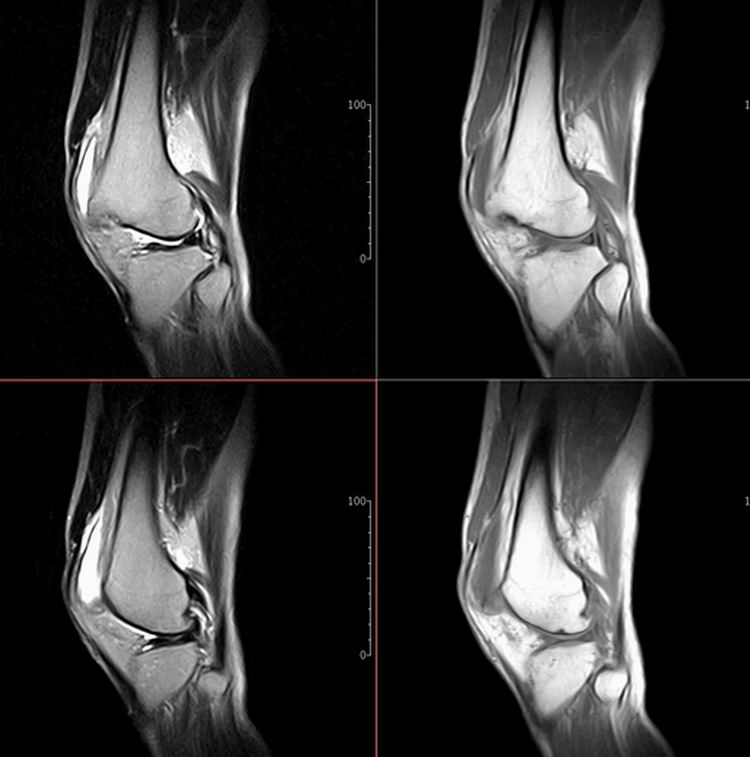

标题: MRI1910:M 687Y。近日因外伤疼痛,而就诊。

m 687y。近日因外伤疼痛,而就诊。有外侧副韧带损伤吗??因片子较差各位请包涵。

这算什么位置呢?矢状位?冠状位?

关节退行性变伴股骨外髁关节面下囊肿,不除外剥脱性骨软骨炎.关节积液,髌骨软化症

体位不标准。关节退变伴关节积液。

1)膝关节骨质退行性改变。

2)由于体位的关系不能确定有外侧副韧带的损伤。

关节退变伴关节积液,外侧副韧带的损伤

关节积液,外侧副韧带的损伤